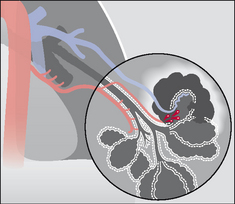

The lung has two distinctive and separate blood supplies (Fig. 30.1):

image Low pressure pulmonary arteries which end in a network of capillaries supplying the alveoli only.

image High pressure bronchial arteries arising from the aorta. Their sites of origin can vary—usually from the proximal descending aorta. Typically, two bronchial arteries supply the left lung and a single bronchial artery supplies the right lung. These arteries feed the bronchial walls up to and including the terminal bronchioles. They also supply the connective tissue of the lung as well as the visceral pleural membrane.

Figure 30.1 The two separate blood supplies to the lungs. The bronchial arteries (high pressure) arise from the aorta. The pulmonary arteries (low pressure) arise from the right side of the heart.